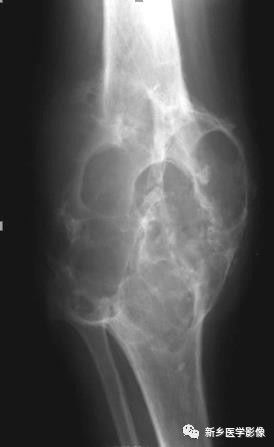

骨骼变形X线图像

膝部正位片示股骨下端与胫、腓骨上段膨大、变形,内部不规则泡状分隔